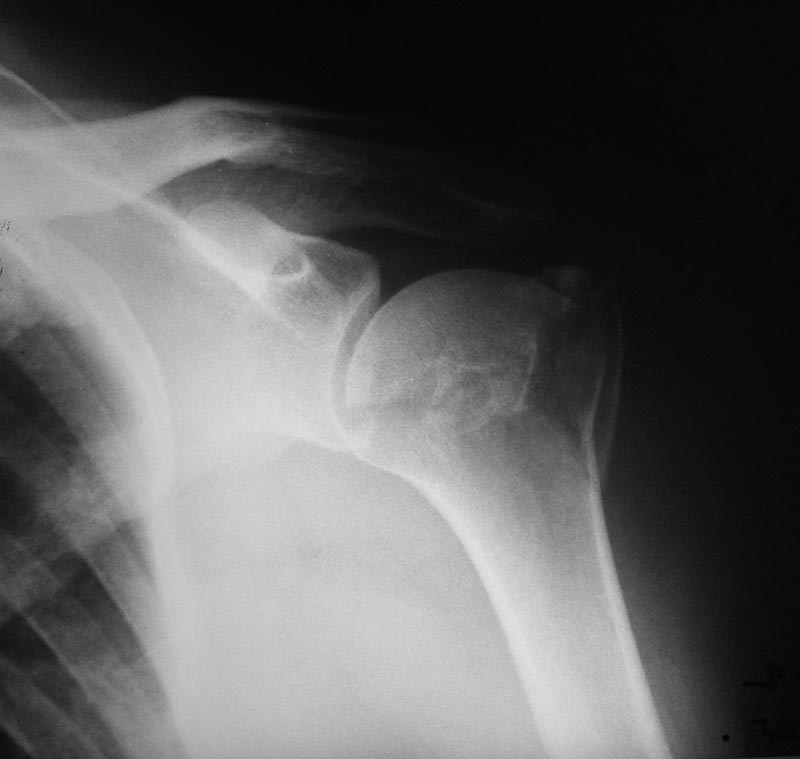

[Ortho] Перелом шейки плеча

Пациентка 60 лет. Работает художником. Хотелось бы услышать мнение:

оперативное или консервативное лечение.